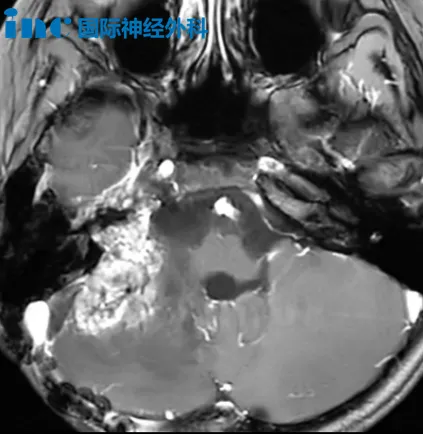

今天,还有一位特别的老患者收到了巴教授的最新随访报告。1年前的平安夜,她正是在巴教授主刀下,于“手术禁区”脑干完成海绵状血管瘤切除术。如今,她带着一份令人忐忑的复查报告再次找到巴教授。

然而,术后一年复查时,影像报告却提示:“脑干新发海绵状血管瘤,大脑镰亦见一新发病灶”,当然检查报告也提到仅供临床医生参考。因此,究竟是何情况,还需找到主刀的巴教授才能最终确定。当巴教授抵达苏州当日,便为她进行视频随访,以尽早解开她的疑虑。

好消息传来——“没有复发,也没有新发。”

教授仔细看过核磁后,对于影像上的疑虑,巴教授也做了详细的解答:之前海绵状血管瘤所在的位置,现在已经完全看不到海绵状血管瘤了,它已经彻底消失。右侧额叶,尤其是靠近大脑镰的区域,通常可以看到钙化,这一点放射科医生应该能够正确区分,不应被误判。

此外,巴教授指出,类似情况并不少见——很多患者在手术后,因影像科医生未能准确区分新发出血与含铁血黄素沉淀,从而承受不必要的心理压力。“其实根本没有新发病灶。”